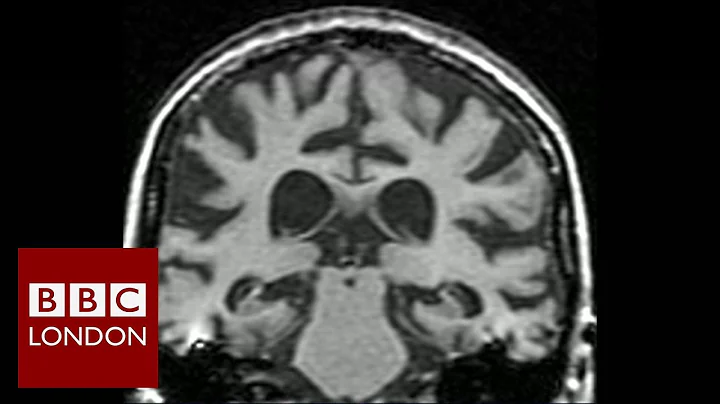

We've been looking at some technological approaches to better understand and help tackle dementia. Subscribe HERE ...